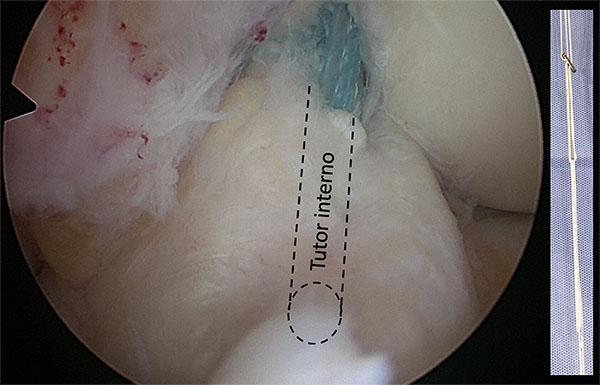

3. Tutor interno

Se realiza un túnel femoral y tibial utilizando una mecha que permita el paso de un botón de fijación cortical (en nuestro caso 4.5 mm). El tutor interno que se utilizará para la aumentación del ligamento (en este caso utilizamos una malla entrelazada de fibras ultra-resistentes) se fijará a nivel femoral con un botón cortical regulable (ACL TightRope) (fig. 4a, video 4).

Puede resultar útil una guía femoral de afuera-adentro, que permita apoyarse directamente sobre el sitio de inserción. Para el túnel tibial la guía se puede colocar sobre el remanente ligamentario distal (fig. 4b, video 4).

Figura 4: Tunel femoral (a) y tibial (b) para pasaje del tutor interno. Se utiliza una mecha del diametro necesario para pasaje del boton cortical (en este caso, 4.5 mm).

4. Fijación de las suturas

Se pasan las suturas del ligamento por el túnel femoral y luego el botón cortical con el tutor interno para la aumentación. Este puede pasar por delante del ligamento (realizando una incisión a las fibras distales) o por dentro de las fibras del ligamento (fig. 5, video 5).

Figura 5: Tutor interno pasado por dentro de las fibras del LCA. La maya entrelazada de fibras ultra-resistentes se fija en el femur utilizando, en este caso, un boton de fijación cortical.

El tutor interno se puede fijar en la tibia utilizando un tornillo biocompuesto (SwiveLock) con la rodilla en extensión (video 5, fig. 6).

Figura 6: Fijación del tutor interno con la rodilla en extensión utilizando un tornillo biodegradable.

Las suturas del LCA se fijan a la cortical femoral externa con los hilos del botón utilizando un baja-nudo (fig. 7, video 6).

Figura 7: Las suturas de ambas bandas del LCA se anudan con los hilos del botón cortical utilizando un baja nudo.